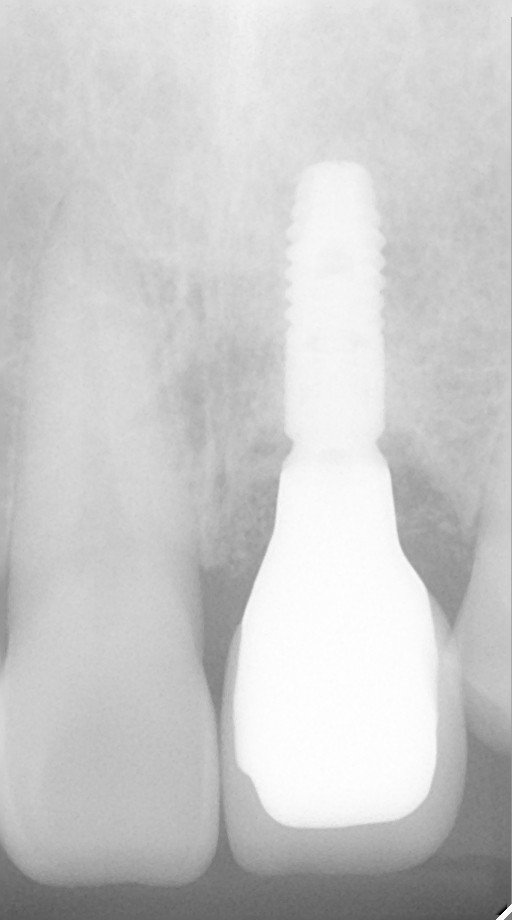

インプラント治療の症例紹介⑨

Before

After

主訴

前歯が揺れる、咬むと痛い

治療内容

抜歯後骨造成手術を行い、その後インプラント埋入手術を行いました。

治療費

462,000円(税込)

治療期間

7ヶ月

通院回数

15回

想定されたリスク

※経年的な歯肉退縮の恐れ.インプラント周囲炎の恐れがありました。

外傷により歯根破折を生じたケース。骨欠損が大きかったので骨造成術を行い、審美ゾーンにインプラント補綴を行った症例です。